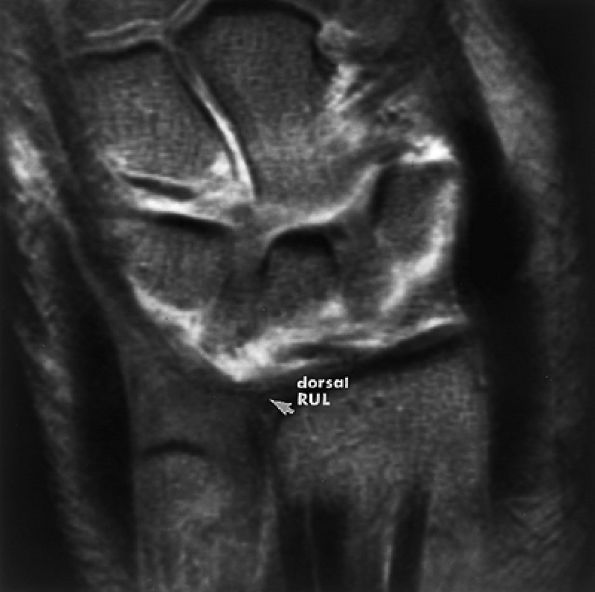

FIGURE 10.73 ● Anatomy of the scapholunate ligament complex on three separate coronal images. (A) Volar component. (B) Membranous component. (C) Dorsal component. (D) On a corresponding axial image all three components of the scapholunate ligament complex are demonstrated. The dorsal scapholunate ligament is horizontally oriented and is perpendicular to the joint. The fibers of the membranous portion of the scapholunate ligament course peripherally and obliquely from the scaphoid downward toward the lunate in a dorsal-to-volar direction. The volar scapholunate ligament courses obliquely from the scaphoid downward to the lunate. This arrangement of scapholunate ligament fibers biomechanically hinges the joint dorsally at the level of the dorsal transverse fibers. In forced extension, scapholunate ligament failure initiates in its volar aspect. S, scaphoid; L, lunate; v, volar component; m, membranous component; d, dorsal component. Arrows correspond to the course of each component of the scapholunate ligament.

|